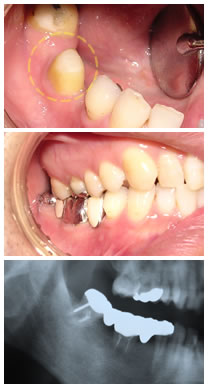

移植後2ヶ月ブリッジ形成時(上の写真)

ブリッジ装着後(真ん中の写真)

術後6ヶ月後レントゲン(下の写真)